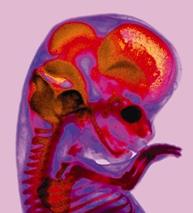

některé obrázky čerpány z http://mimiblog.cz/kt/tyden/1